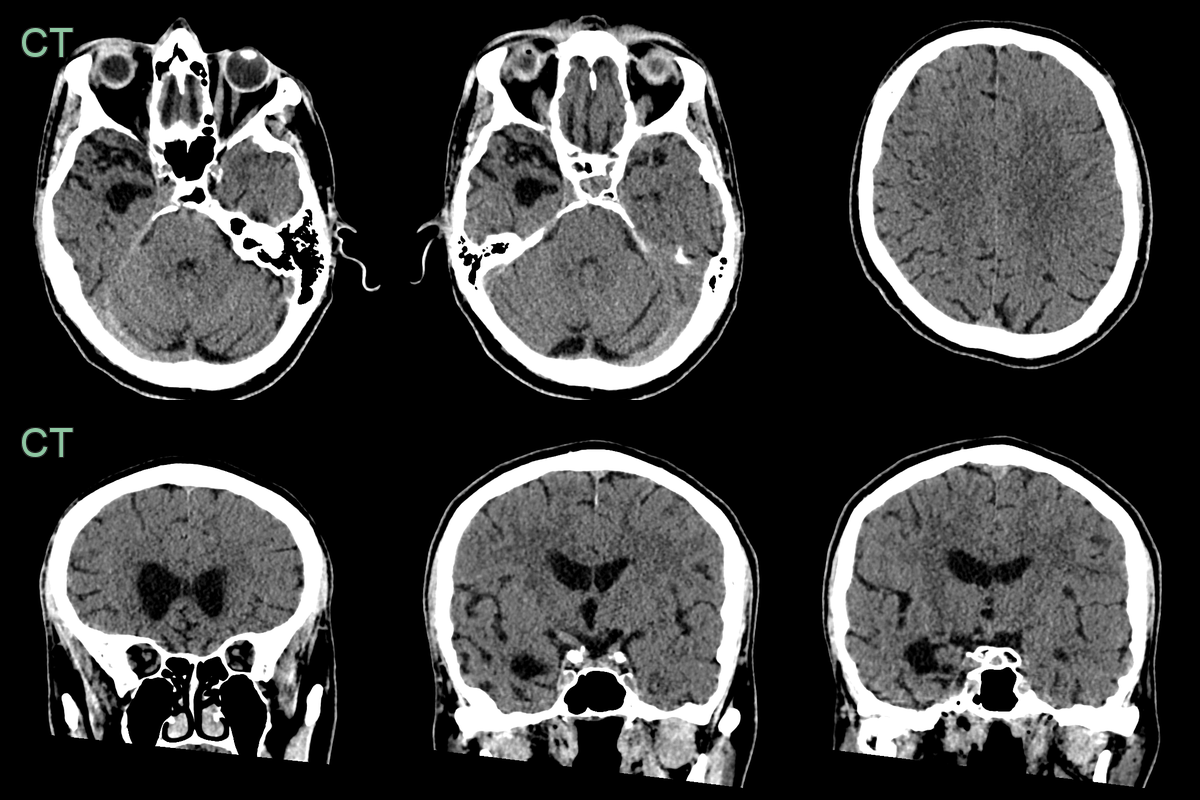

- 60-year-old patient presented with behavioural change and speech changes.

- MRI showed left frontal and temporal atrophy; the superior frontal gyrus was knife-blade thin.